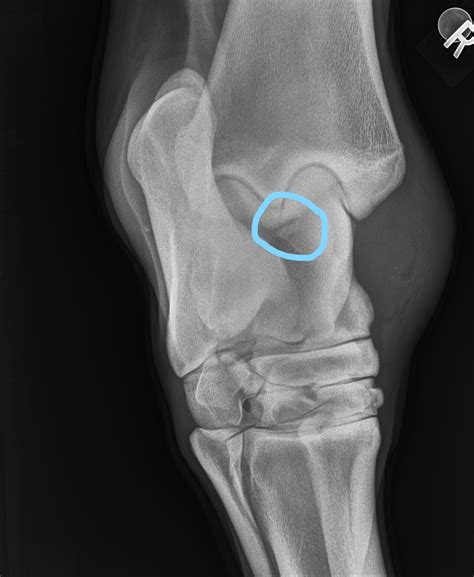

Why Osteochondritis Dessicans Is Affecting Young Athletes More Now

January: Osteochondritis dessicans (OCDS) - Swiftsure Equine